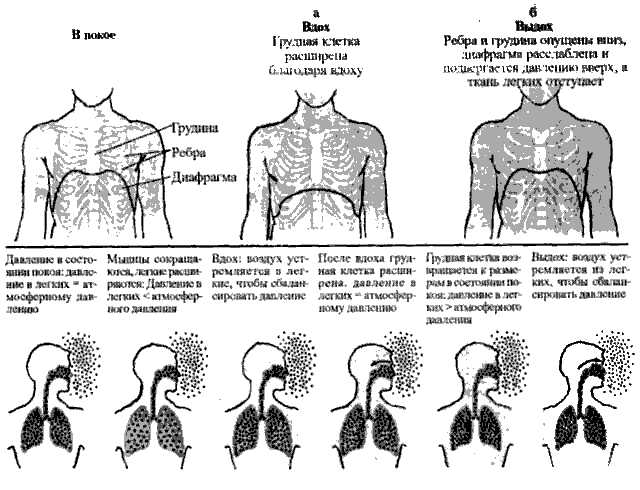

1.5. Динамика дыхательного механизма

Дыхательный цикл определяется как пауза между двумя вздохами, плавный переход от вдоха к выдоху через малозаметный интервал времени. В процессе каждого цикла в легких и грудной клетке происходят изменения, которые определяются как динамика дыхательного механизма. Динамика вдоха и выдоха показана на рис. 4.

Из рисунка видно, как движение легких и диафрагмы может увеличивать и уменьшать размер грудной клетки.

Диафрагма и внешний межреберный мускул (мышцы между ребрами) задействованы в активном процессе вдыхания. Итак, вдыхание является активным процессом, в то время как выдыхание – пассивным, включающим в себя расслабление дыхательных мышц и естественную упругую «отдачу» легочных тканей при обычном дыхании в состоянии покоя. Но при затрудненном или форсированном (как в случае пранаямы) дыхании выдох становится более активным, и в него вовлекаются мышцы в области грудной клетки.

В процессе вдоха объем грудной клетки может увеличиваться по трем направлениям: боковому (поперечному), передне-заднему (п-з) и вертикальному, как изображено на рис. 4 (а и б). На нем можно заметить, что как раз боковое и п-з движения совместно приносят обычно изменение в объеме 40% от общего объема легких, в зависимости от положения тела – сидя, стоя или лежа.

Движение в боковом направлении (нижняя часть грудной клетки) происходит, когда ребра покачиваются вверх и наружу, наподобие движений ручки ведра. Движение в направлении п-з (верхняя часть грудной клетки) происходит, когда грудина покачивается вверх и вперед, наподобие движений рукоятки водного насоса. В то же время движение по вертикали происходит, когда диафрагма сокращается, уплощаясь вниз в направлении брюшной полости, наподобие движений велосипедного насоса. Одновременное движение по всем этим трем направлениям позволяет легким расширяться и растягиваться в процессе вдоха, поскольку увеличившийся объем грудной клетки создает для этого достаточно пространства, как показано на рис. 4 а.

Рис. 4. Процесс вдоха и выдоха, (а) Размеры легких и грудной клетки увеличиваются во время дыхания, создавая отрицательное давление, в результате чего воздух загоняется в легкие, (б) Во время выдоха объем легких уменьшается, тем самым воздух вытесняется из легких.

Выдох завершается, когда все описанные выше движения совершаются в обратном направлении. Диафрагма расслабляется и возвращается в свое обычное положение, в виде направленного вверх свода. Внешние межреберные мышцы расслабляются, заставляя ребра и грудину опускаться обратно, в их исходное положение. Затем эластичная природа легочных тканей заставляет их возвращаться к своему размеру в состоянии покоя, как показано на рис. 4 б.